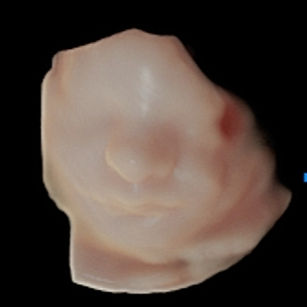

Baby’s Growth & Size

Weight: About 3–3.5 pounds (1.4–1.6 kg), the size of a Coconut!

Length: Around 16 inches (40–41 cm) from head to heel.

Baby is gaining about ½ pound (225 g) per week, mostly fat and muscle.

Skin: Becoming smoother as fat builds up underneath; baby is starting to look plumper and less wrinkly.